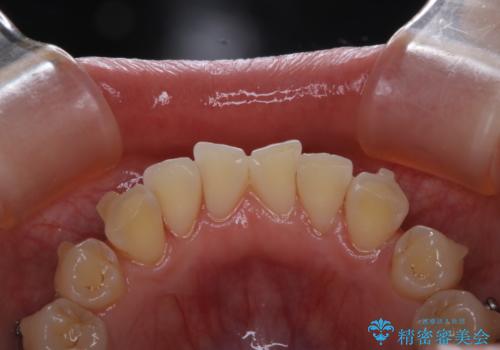

インビザラインでの治療中の患者様のクリーニング前後写真です。

矯正治療中は虫歯や歯周病リスクが高くなります。

矯正治療(インビザライン、ワイヤー矯正)の経過で来院の際、ご希望の場合はクリーニングの予約も同時に取ることが可能です。

ぜひ定期的なクリーニングをおすすめします。